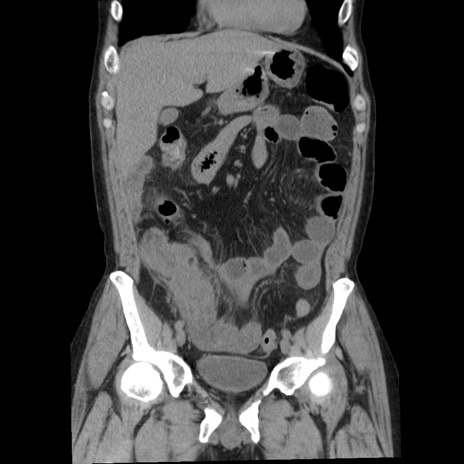

症例29(冠状断像)

【症例】40歳代男性

【現病歴】2日前から胃痛あり。徐々に周期的な激痛に変化した。本日になっても激痛があるため受診。

【身体所見】意識清明、BT 38-39℃台あり、腹部:膨満、やや硬、右下腹部に圧痛あり。

【データ】WBC 8500、CRP 23.26